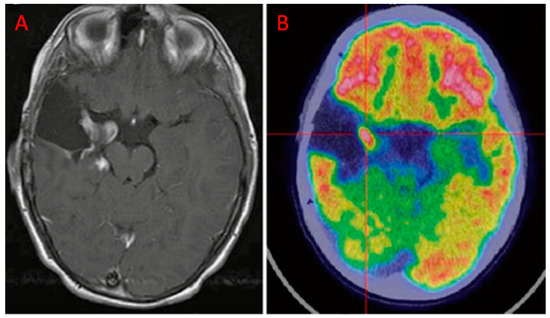

| Valentini et al. [20] | 2017 | R | 12 (48 biopsy specimens) | GBM | PET/CT | DWI, DTI, DSC-PWI, MRSI | Highest values of rCBV, Cho/Cr, Cho/NAA, proportional decrease of SUVmax with increasing distance from the CE region. At histological examination, the CE region showed maximum tumor histological malignancy and presented the maximum values of rCBV, Cho/Cr, Cho/NAA, LL and SUVmax. |